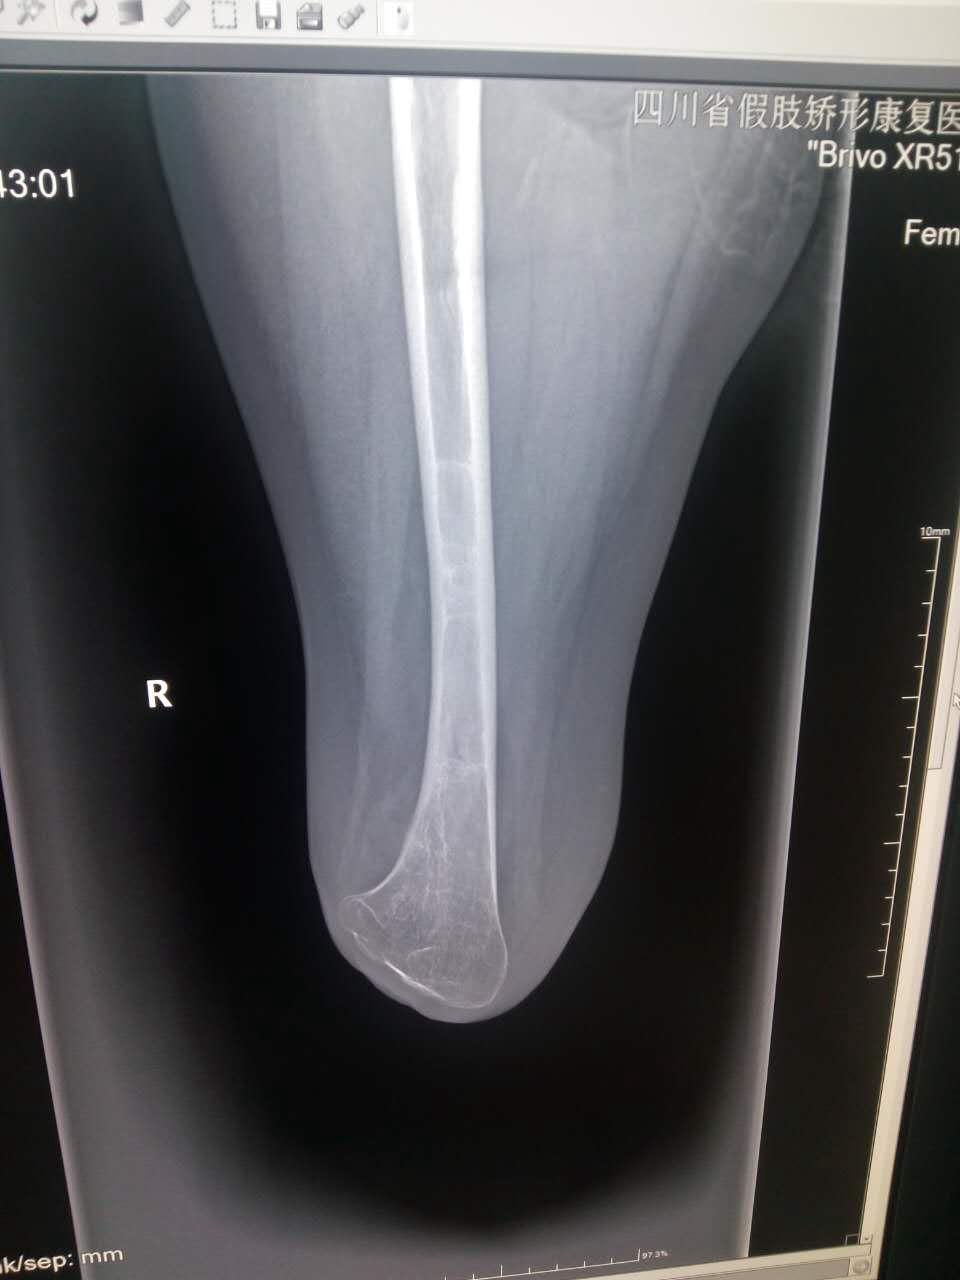

截肢二十多年,请各位老师指点一下这张x光片

骨髓腔未看到透明线啊,再者多数骨折线会累及骨皮质的,特别是成年人。

右下肢股骨以下部位缺如。股骨未见明显异常。